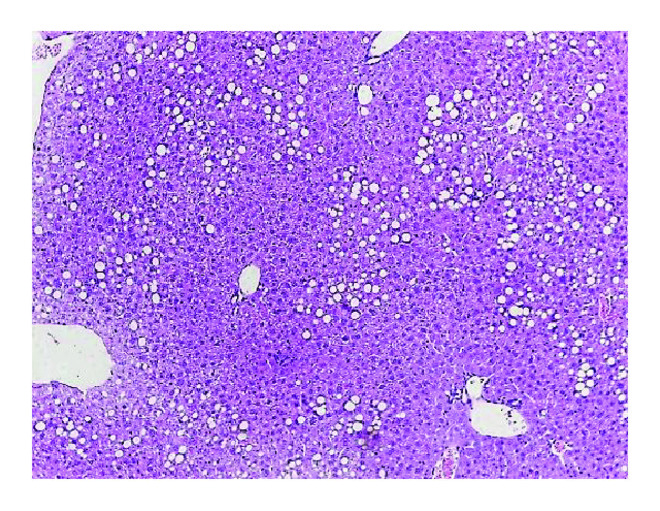

3.3. Improvement of NAFLD in Pioglitazone-Treated CAR-/- Mice Regardless of Blood Concentration of Pioglitazone

Because pioglitazone is mainly metabolized by CYP2C8 and CYP3A4 in vitro [17], serum concentrations of pioglitazone may be affected by CAR activity. Therefore, we measured the concentration of pioglitazone in three groups with different CAR activity. The mean concentrations of pioglitazone were 14.9 ± 11.5, 2054.0 ± 1132.9, and 4109.7 ± 606.2 ng/mL in CAR+/+ with TCPOBOP, CAR+/+, and CAR−/− mice, respectively. Because TCPOBOP strongly stimulates CAR activity, we could not properly evaluate the effect of pioglitazone under TCPOBOP treatment conditions. In addition, as pioglitazone induced expression of CAR target genes (CYP2B10 and CYP3A11, Supplementary Figure 1), we thought that the existence of CAR gene itself might interfere with the interpretation of the effect of pioglitazone on NAFLD. Thus, further analysis of the effects of pioglitazone on NAFLD by CAR activity was performed only in CAR+/+ and CAR−/− mice. To confirm whether the improvement of hepatic steatosis after pioglitazone in CAR−/− mice resulted from a higher concentration of pioglitazone or was related to the absence of CAR itself, we made similar serum pioglitazone concentrations for both CAR+/+ and CAR−/− mice. We administered different concentrations of pioglitazone (10, 20, and 30 mg/kg) for 2 weeks with the HF diet to CAR+/+ and CAR−/− mice and measured the pioglitazone concentration in the blood (Figure 3(a)). CAR−/− mice showed approximately 3–10-fold higher concentrations of pioglitazone compared to CAR+/+ mice after receiving the same dose of pioglitazone. Based on these results, we administered 10 and 20 mg/kg of pioglitazone in CAR+/+ mice and 1 and 3 mg/kg of pioglitazone to CAR−/− mice for 2 weeks in conjunction with a HF diet. We obtained similar serum concentrations of pioglitazone in CAR+/+ and CAR−/− mice (Figure 3(b)). Next, we compared the hepatic steatosis of CAR−/− mice treated with 1 and 3 mg/kg of pioglitazone to that in CAR+/+ mice treated with 10 and 20 mg/kg of pioglitazone. Despite the similar serum concentrations of pioglitazone between CAR+/+ and CAR−/− mice, a significant improvement in hepatic steatosis was persistently observed in CAR−/− mice (Figure 3(d) versus 3(g), 3(e) versus 3(h)). In CAR+/+ mice, pioglitazone treatment showed no improvement in fatty liver compared with control mice (Figures 3(d), 3(e) versus Figure 3(c)). On the other hand, pioglitazone treatment was effective in the improvement of fatty liver in CAR−/− mice compared to the control mice (Figures 3(g), 3(h) versus 3(f)).